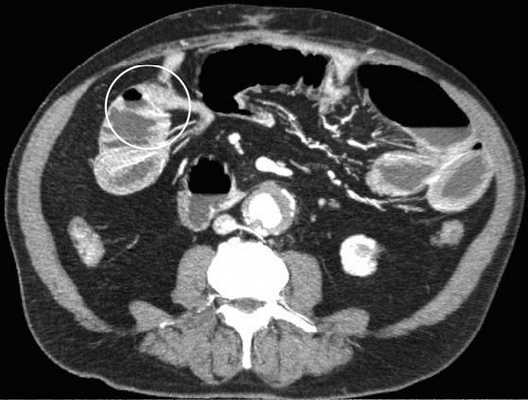

Мальротация кишечника (нонротация) у мужчины 39 лет.

(а, б) Тощая кишка — прямое продолжение двенадцатиперстной (стрелка, а), отсутствуют нормальные 3-й и 4-й сегменты двенадцатиперстной кишки, а также двенадцатиперстно-тощекишечный переход (звездочка, б).

(в, г) Петли тонкой кишки (прямые стрелки) лежат в левой половине брюшной полости, а ободочная кишка (изогнутые стрелки) — в правой половине. Заворот средней кишки у мальчика 11 лет.

Врожденная мальротация кишечника обусловлена нарушением нормальной ротации первичной кишки в направлении против часовой стрелки. Среди широкого разнообразия вариантов мальротации в клинической практике наиболее часто встречают полное отсутствие ротации (нонротация). При этом состоянии тощая кишка служит прямым продолжением двенадцатиперстной, при этом отсутствуют 3-й и 4-й сегменты двенадцатиперстной кишки и двенадцатиперстно-тощекишечный переход. Петли тонкой кишки лежат в левой половине брюшной полости, а ободочная кишка — в правой половине. При завороте средней кишки ножка брыжейки сужена, а двенадцатиперстно-тощекишечный переход (местонахождение связки Трейтца) чаще расположен низко, по правую сторону от средней линии. Такие условия приводят к перекручиванию неправильно фиксированной тонкой кишки, а верхние брыжеечные артерия и вена располагаются в короткой и суженной ножке брыжейки.